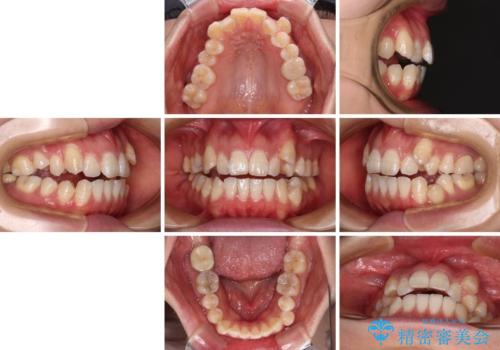

八重歯と開咬の抜歯矯正 ワイヤー装置を併用したインビザライン矯正治療

- 咬み合わない前歯と八重歯などのデコボコを気にして来院された患者様です。

上下前歯の位置を比較すると上顎が前方にあり、デコボコ改善でより上顎が前方に行く可能性があります。

開咬の改善にはインビザラインが有効であり、インビザライン単体での治療を検討しましたが、上顎前突を回避するために上顎左側第一小臼歯抜歯を行うこととしたため、補助装置とワイヤー矯正を併用した上で、インビザラインによる矯正治療を行うこととしました。

インビザライン矯正治療では、臼歯の圧下による前歯部の早期接触が大きな問題となっています。開咬では、その臼歯圧下を逆手にとって前歯部の非接触を改善させることができます。